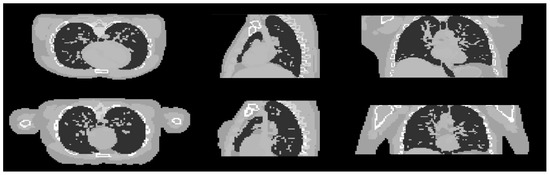

Figure 10.

Cross sectional slices of the male (top row) and female (bottom row) phantoms in the three axes.